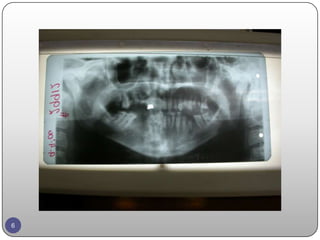

EXAMINATION  Chief complainrestoring the esthetic and the function  Patient fits well  46, 45 are missing teeth. 5